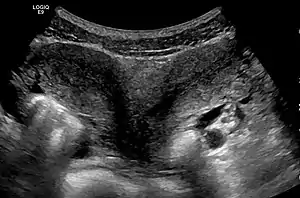

| Ultrasound showing didelphys | |

Helpful techniques to investigate the uterine structure are transvaginal ultrasonography and sonohysterography, hysterosalpingography, MRI, and hysteroscopy. More recently 3-D ultrasonography has been advocated as an excellent non-invasive method to evaluate uterine malformations.[4]